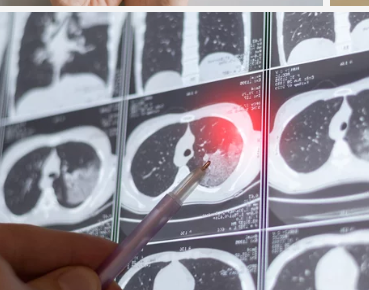

② 중증 폐기흉 – 흉관 삽입(공기 배출 치료)

✔ 폐가 심하게 눌려 있거나 호흡 곤란이 심할 경우, 흉관 삽입이 필요

✔ 가슴에 관을 삽입하여 폐 주위에 찬 공기를 배출(흉관 삽입술)

✔ 대부분 2~5일간 흉관을 유지하면서 폐가 정상적으로 펴지는지 확인